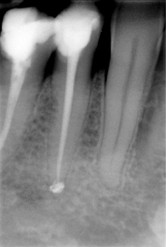

paradontologický zápal paliatívne endodontické ošetrenie